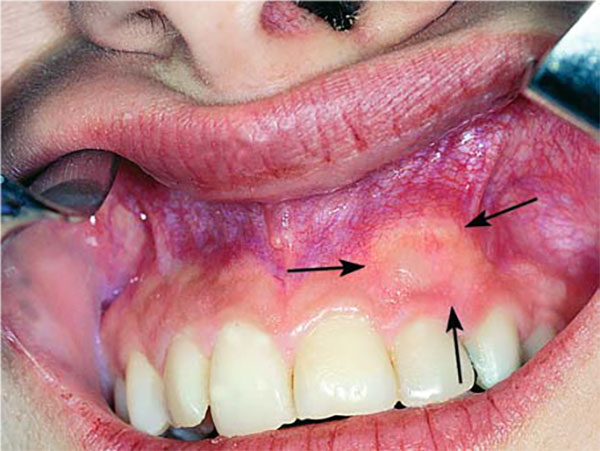

معمولا افرادی که با نهفتگی دندان نیش مراجعه میکنند یک دندان نیش شیری در دهان دارند که به دنبال پوسیدگی دندان شیری و برای جایگزینی آن دندان شیری مراجعه نمودهاند و متوجه وجود نیش نهفته میشوند. سناریوی دیگر این است که به دنبال وجود برجستگی در کام یا لب به مطب ها مراجعه می کنند. و یا اینکه والدین و یا دندانپزشک کودک متوجه عدم رویش دندان نیش دائمی شده و بیمار را جهت درمان به متخصص جراح فک و یا ارتودنسی ارجاع می دهند. متخصصین ارتودنسی معمولا توصیه می کنند تا کودکان را در سن ۷ سالگی برای رادیوگرافی کلی جهت بررسی روند رشد دندانها و ناهنجاری ها نزد پزشک ببرند. عمدتا، اصلی ترین دلیل رشد دندان نهفته نبود فضای کافی در فکین است برای باز کردن فضای فکین می توان به ارتودنتیست مراجعه نمود تا از دستگاه اکسپندر یا بازکننده کام برای رفع این مشکل استفاده نماید.عوامل موثر در درمان نیش نهفته

عواملی که بر درمان نیش نهفته تاثیر می گذارند عبارتند از: سن بیمار، محل نهفتگی (لبیال یا پالاتال)، زاویه و عمق نهفتگی، میزان فضای قوس دندانی و … از جمله درمانهای شایع برای هدایت نهفتگی به داخل قوس دندانی میتوان به مواردی اشاره کرد مانند کشیدن دندان نیش شیری، باز کردن فضای رویش نهفتگی با ارتودنسی اکسپوژر جراحی تاج دندان نهفته و هدایت آن به داخل قوس با نیروی ارتودنس.درمان نیش نهفته با ارتودنسی

جهت درمان نهفتگی دندان نیش می توان از ارتودنسی ثابت استفاده .کرد در این صورت یک جراحی ساده مورد نیاز است تا دندان نیش نمایان شود. سپس با نصب براکت ارتودنسی روی دندان با زنجیر مینیاتوری به سیم ارتودنسی متصل می شود. پس از مدتی می بایست مجددا نزد پزشک رفت تا توسط بند رابری به ،زنجیر نیروی بیشتری ایجاد کند. با این روند درمان ارتودنسی ناهنجاری دندان نهفته از حالت افقی به عمودی و در جای مناسب هدایت خواهد شد. دوره درمان حدود یک سال به طول می انجامد. در پایان ،درمان بیرون آمدن نهفتگی دندانی را مشاهده خواهید کرد. معمولا این جراحی با بی حسی موضعی صورت می پذیرد. حدود ۴۵ دقیقه جراحی و نصب براکت، به طول می انجامد. اگر هر دو دندان نیش در حالت نهفته قرار داشته باشند، این زمان بیشتر خواهد شد.نمونه ی رادیوگرافی OPG مربوط به دندان نیش نهفته